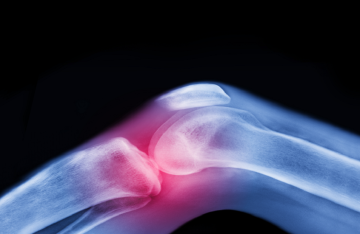

العلاج الأقوى لآلام المفاصل قبل اللجوء إلى الأدوية والجراحة